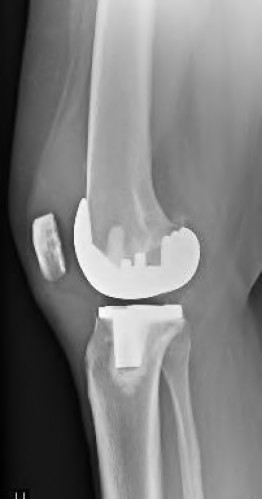

A 72-year-old female presents with progressive left thigh and knee pain for the last year. 5 years ago she sustained a femoral neck fracture treated with the implant seen in Figures A-C (current radiographs). The thigh pain is worse with weight-bearing. C-reactive

protein and erythrocyte sedimentation levels are within defined limits. Which of the following is the most likely cause of her pain?